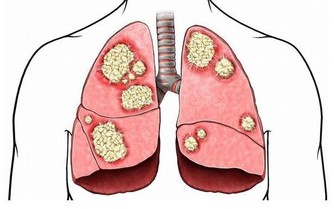

1、導致五臟中毒:長期便秘,毒素在身體內不斷地積聚,是體內五臟中毒現象,降低五臟功能,最終可能有小化大,造成其他疾病。